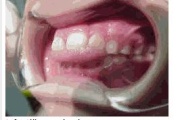

Ravijärgne seis. Jäävhammas on täielikult lõikunud.

) Röntgenülesvõte. Ülemise esimese jäävmolaari lõikumine on takistatud 2. piimamolaari tõttu

Esimese jäävmolaari ektoopiline lõikumine